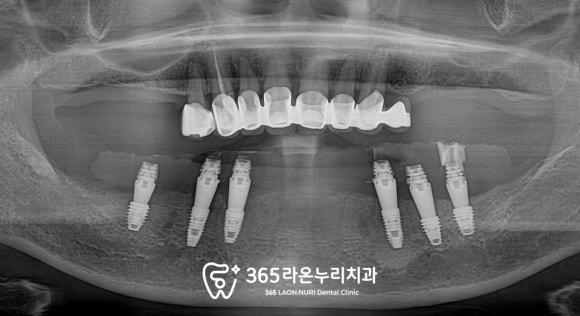

■ 3. 당일 임시치아

임플란트만 심고 끝이 나는 것이 아닌

당일 임시치아 연결까지 해드려야겠죠?

이건 의사들 사이에서도

상당히 고난도에 속하는 편이고,

그만큼 구강에 대한 이해가 높아야 가능한 것인데

저는 CAD-CAM 마스터 클래스와

기공 관련 세미나를 여러개 들어오면서

조금이라도 나은 진료를 해드리기 위해

노력해왔던 것이 이제는 빛을 발하는 것 같습니다.

무튼 이렇게 당일 임시치아를 해드리기 위한

과정을 거쳐 수술 날짜에 맞추어

준비가 끝나고 나면

어버트먼트를 연결하고

그 위로 임시치아도 올려드립니다.